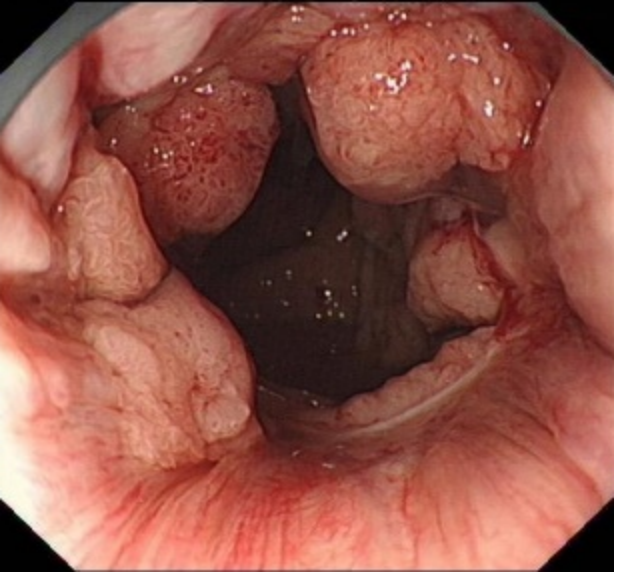

确定是罕见大面积直肠-肛管侧向发育型肿瘤——肿瘤位于肛门齿状线至距离肛门口10cm,而且环周生长,病变肛侧缘已突破肛门齿状线,病变面积大,血管丰富。

▲环周生长的肿瘤